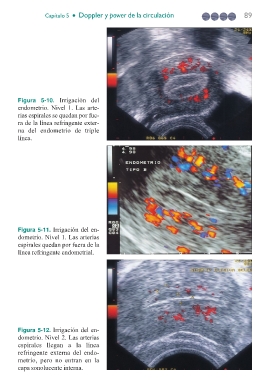

Figura 5-10. Irrigación del

endometrio. Nivel 1. Las arte-

rias espirales se quedan por fue-

ra de la línea refringente exter-

na del endometrio de triple

línea.

Figura 5-11. Irrigación del en-

dometrio. Nivel 1. Las arterias

espirales quedan por fuera de la

línea refringente endometrial.

Figura 5-12. Irrigación del en-

dometrio. Nivel 2. Las arterias

espirales llegan a la línea

refringente externa del endo-

metrio, pero no entran en la

capa sonolucente interna.